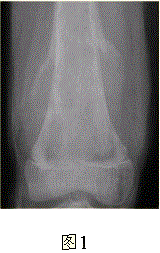

问题 患者男,16岁,左大腿下部疼痛伴肿胀2个月,逐渐加重。自感左膝上方胀痛,尤以夜间为著,伴行走困难。既往史及家族史无特殊。查体:左大腿下部明显肿胀,皮温较对侧升高。碱性磷酸酶明显增高。股骨平片及MRI见下图。 你认为对定性诊断有价值的征象是

选项 A.病变边缘模糊,内部信号不均 B.病变边缘骨皮质完整 C.病变周围可见软组织肿块 D.病变边缘可见骨膜反应,Codman三角形成 E.MR示病变周围骨髓明显水肿 F.病变内未见钙化影

答案 ACDEF